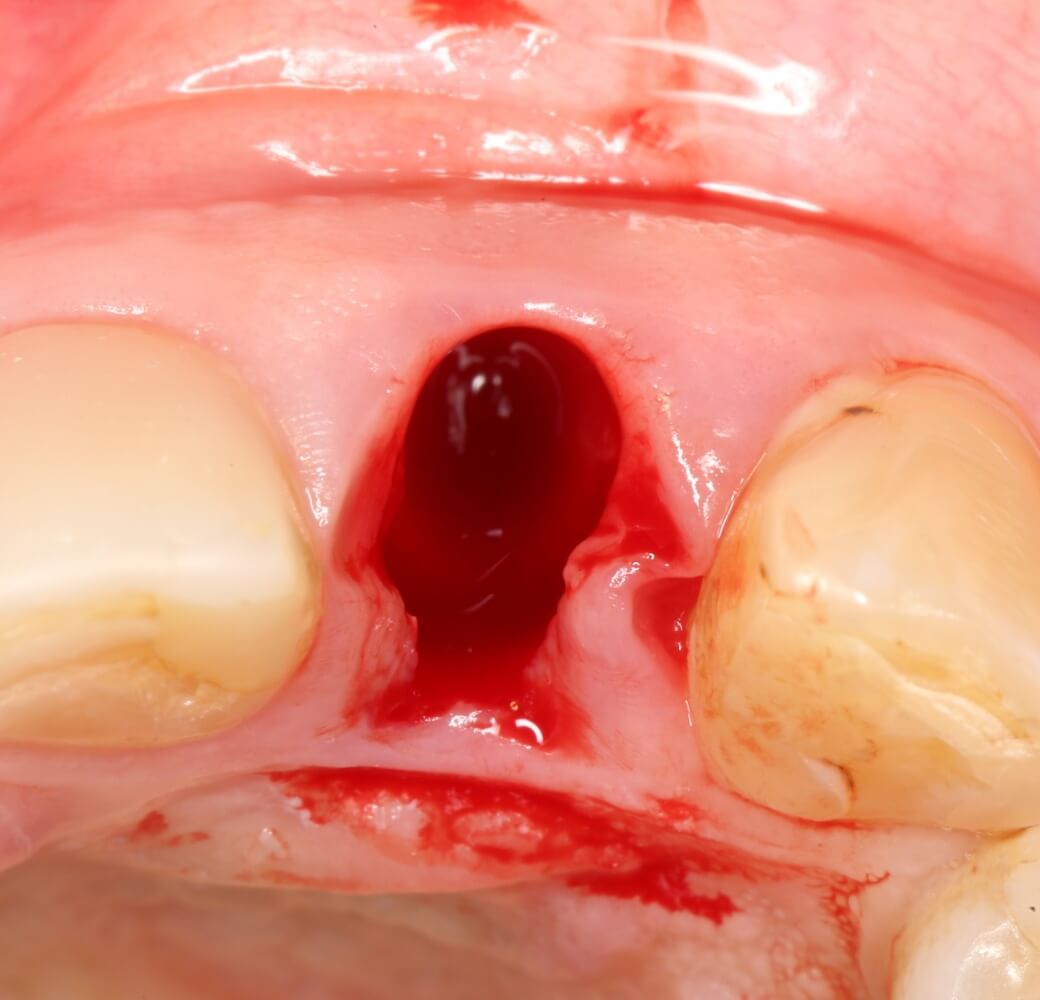

Разумеется, мы можем на неё влиять. Так, немедленная имплантация и превентивная аугментация лунки уменьшают степень атрофии, хотя и не предотвращают ее полностью: